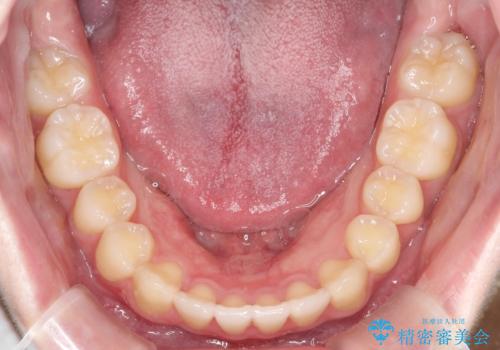

- 前歯のガタガタを主訴に来院されました。

開咬ぎみであったため、しっかりと前歯が噛むように計画を立てて治療をおこないました。

仕上がりも良く、患者様にも満足していただきました。

インビザラインは前歯を噛ませるような開咬の治療も得意としています。